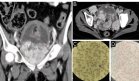

Se realizó ecografía ocular que mostró opacidades vítreas severas con formación de membranas densas en cuadrantes inferiores y desprendimiento vítreo posterior con tracción inferior. Se practicó vitrectomía con toma de muestras para PCR, que resultó positiva para virus Epstein-Barr (EBV) a partir del ciclo 31.4, mientras que fue negativa para otros virus como CMV, herpes y toxoplasma. Los análisis sanguíneos descartaron inmunodeficiencias u otras condiciones asociadas.

El diagnóstico en este caso representó un reto clínico importante que requirió la implementación de técnicas moleculares avanzadas. La confirmación se logró mediante reacción en cadena de la polimerasa (PCR) en tiempo real realizada en muestra de humor vítreo, técnica que demostró ser crucial para identificar la presencia del VEB cuando otros métodos diagnósticos resultaron negativos.